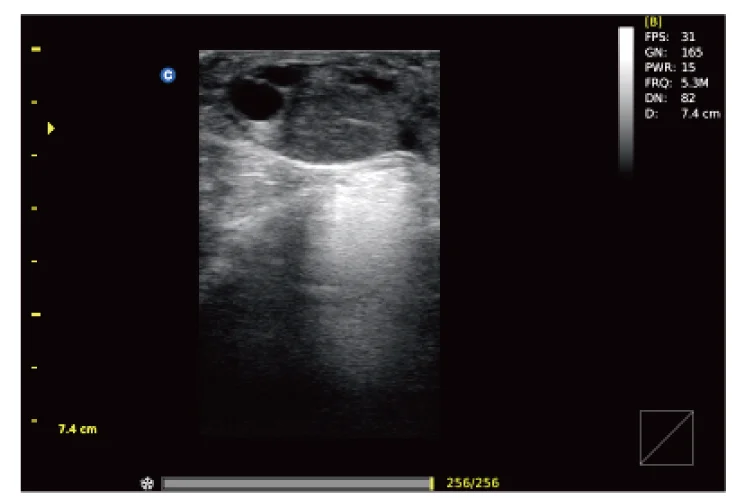

Ultrasound

Wide range of Ultrasound machines that suites a variety of applications from abdominal to rectal scans, we take in consideration how the world is moving towards mobility and mobile applications.

ECO5 VET

Ultra-Portable, Ultra- Affordable, Color doppler

The multi-purpose user presets, comprehensive measurement & report system, built-in EasyView image achieve system, quick image storage / retrieve / transfer, one-button direct print, make the complete workflow better than what you can dream of.